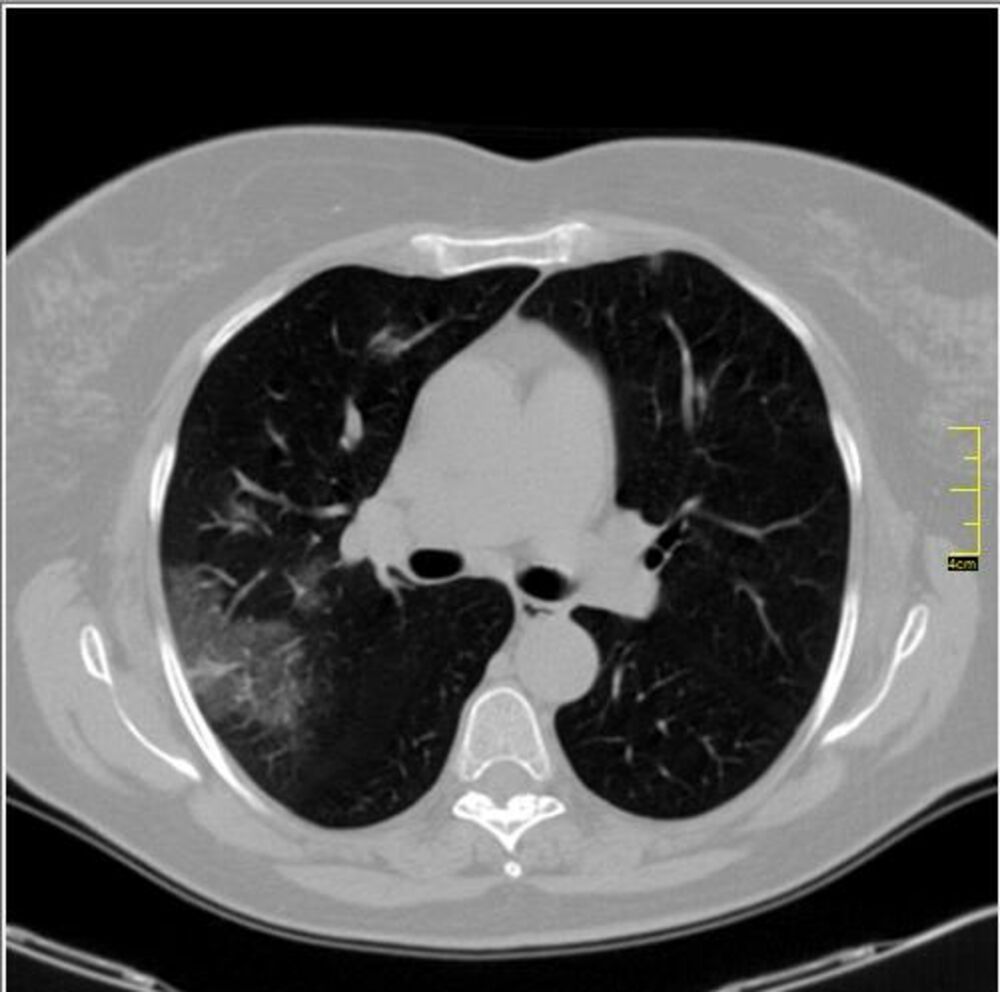

Krenulo je sa divljim sojem. Znamo da je i on imao svoje varijante. Ono što je bilo u samom početku kod nas je ličilo na samu osnovu.

Kada se pogleda pažljivo i deluje divlje, nema neke pravilnosti.

Neki međusoj je bio u leto 2020.